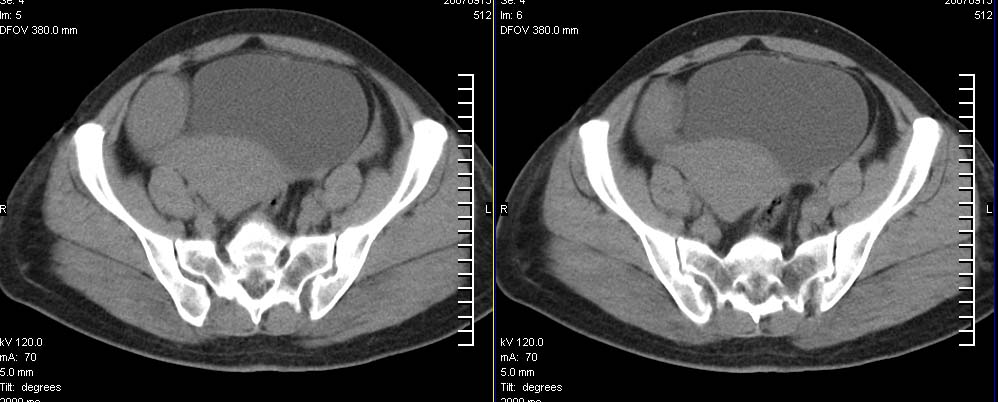

标题: CT9722:卵巢巨大占位,约10*18*21CM大小 [打印本页]

标题: CT9722:卵巢巨大占位,约10*18*21CM大小

卵巢巨大占位,约10*18*21cm大小

右侧卵巢的巨大占位,病灶大部分呈实性,以恶性可能大。

考虑右侧附件来源肿瘤--囊腺瘤可能性大,子宫增大,建议增强扫描.

右侧附件区巨大囊性肿块,边缘光滑,密度较高,左侧缘由多个低密度区,首先考虑囊腺瘤可能。